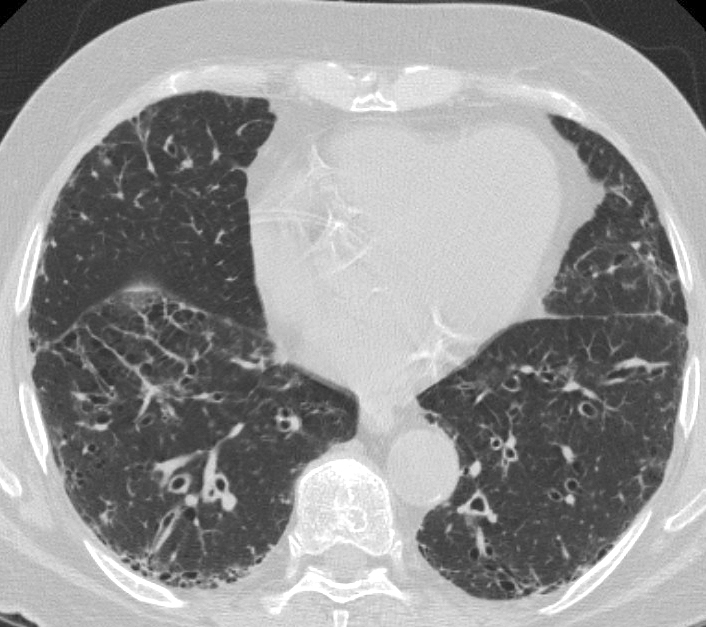

Gallery COPD chronic br CT

chronic br CT